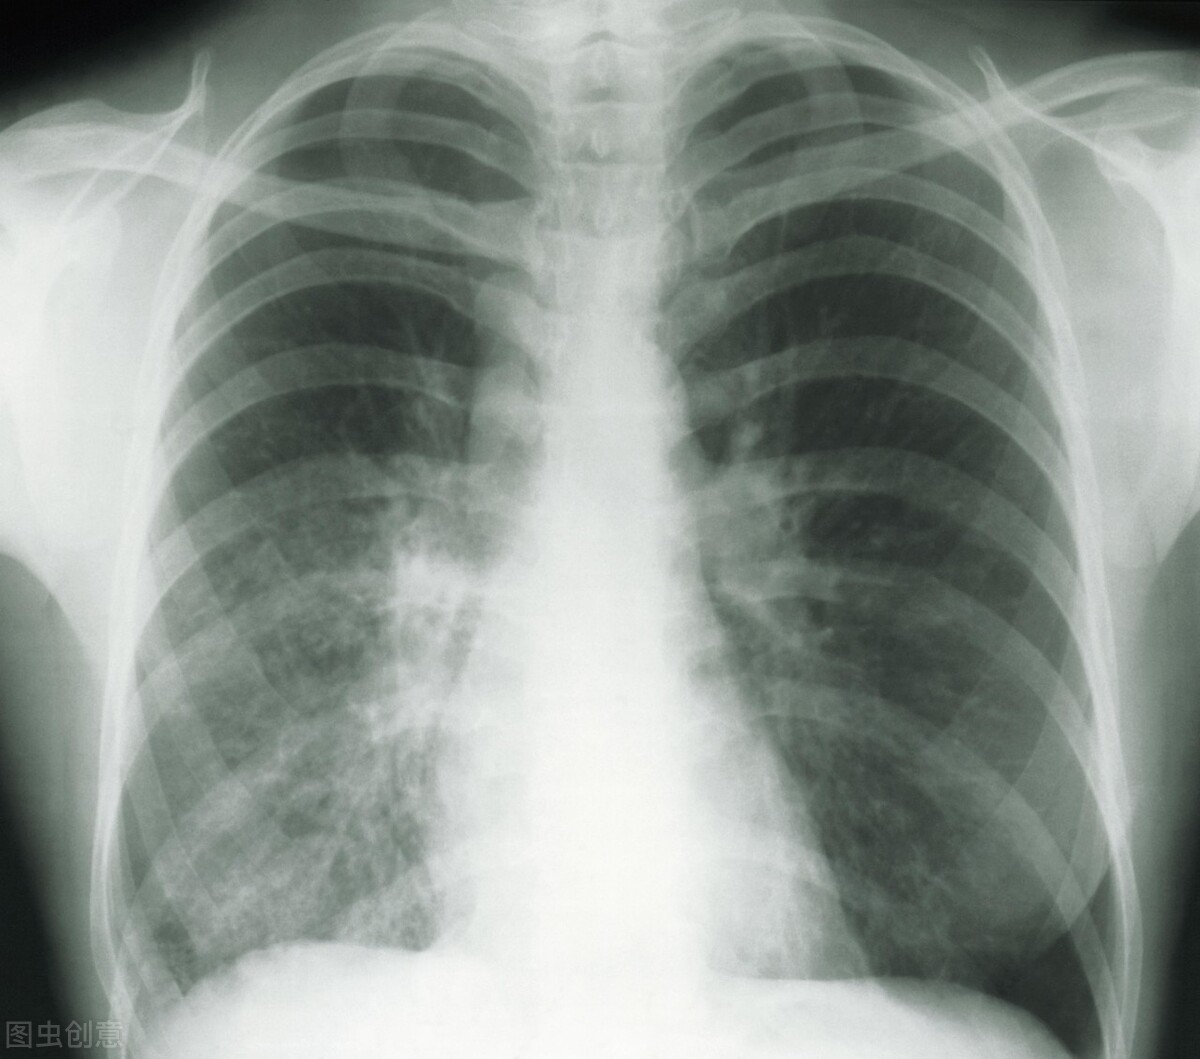

前后经过将近3个月的中药调理,姜某再次复查时,报告提示肺结节和肝囊肿都消失不见(如下图)